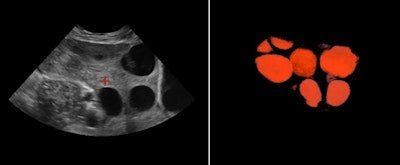

It is a great advantage to diagnose fetal skeletal dysplasia with 3D/4D technology because bone mineralization can be assessed and it is possible to compare bones (e.g., the spine with the skull bone and lavage bone), according to Dr. Peter Conner, PhD, of Karolinska University Hospital in Sweden. With 4D sequences, the fetal movement pattern and soft tissues can be assessed and, hence, malalignments can be diagnosed. Furthermore, with 4D it is possible to see fractures in both the lavage bone and ribs by using skeletal view visualization. In this mode, the skeletal structures are enhanced and soft tissues are suppressed.

A combination of better usage of 3D technology and knowledge of 3D technology in skeletal dysplasia will make it possible to correctly assess and diagnose many skeletal dysplasias in the first trimester. This is a major improvement, as most skeletal dysplasias are not currently diagnosed until the second or third trimester in families without a known family history of the condition, according to Conner. Adaptive volume enhancement technology, which suppresses unwanted signal such as noise/speckle, could also potentially facilitate the early diagnosis of skeletal dysplasias.